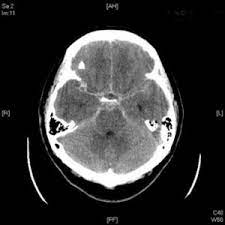

Conferencia: “ Diagnóstico de accidentes cerebrovascular , por neuroimágenes”

Hallazgos estructurales en el cerebro, en paciente afectados por accidentes cerebrovascular, durante esta conferencia nuestro invitado hará una revisión sintética pero básica, sobre los hallazgos más frecuentes en encontrados en imágenes radiológicas, de tomografía axial computarizada [TAC] y la resonancia magnética (RM).